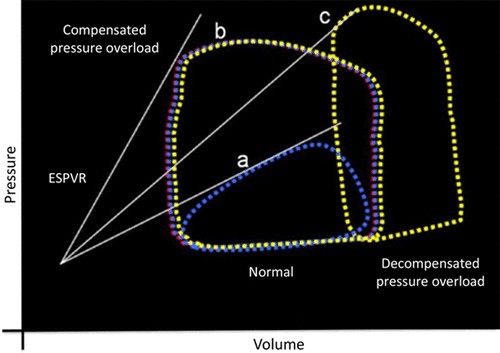

Thể tích tống máu (SV) của thất phải cũng tương đương thể tích tống máu (SV) của thất trái nhưng sức cản của hệ mạch phổi thấp hơn nhiều so với sức cản của hệ động mạch chủ. Điều này dẫn đến công tống máu của TP chỉ bằng 1/6 công tống máu của thất trái. Do sức cản của tuần hoàn phổi thấp nên thất phải tống máu ngay từ giai đoạn đầu tâm thu và tiếp tục tống máu ở cả giai đoạn đầu tâm trương (khi thất trái đã kết thúc giai đoạn tống máu và thất phải đã bắt đầu giãn ra). Do vậy thất phải không có các giai đoạn co đồng thể tích và giãn đồng thể tích (hình 2 - vòng lặp áp lực - thể tích thất phải)

Hình 2. Các vòng lặp Áp lực- thể tích (AT) thất phải thu được qua thông tim (Đường màu trắng(ESPVR) thể hiện mối liên quan giữa Áp lực -thể tích cuối tâm thu thất phải của các vòng lặp với các điều kiện về tiền tải và hậu tải khác nhau. Độ dốc của đường ESPVR phản ánh khả năng giãn ra cuối tâm thu của TP(Ees). Độ dốc cao hơn tương ứng với Ees cao hơn.

Vòng lặp a- Mô tả một vòng lặp AT thất phải bình thường. Phần lớn công năng tống máu của thất phải là để tạo ra động lượng cho dòng máu đi vào động mạch phổi, một phần rất nhỏ là để tao ra áp lực bình thường của thất phải. Ở trạng thái bình thường, khác với với tâm thất trái, TP gần như không có các giai đoạn đẳng tích. Động lượng dòng chảy cao giúp đẩy máu từ TP vào tuần hoàn phổi (nơi có áp lực thấp), vì vậy khi thất trái đã kết thúc giai đoạn tống máu và bước vào giai đoạn giãn đồng thể tích thì TP vẫn tiếp tục tống máu (mặc dù TP đã bắt đầu giãn ra)

Vòng lặp b- Thể hiện tình trạng tăng áp TP mãn tính và TP còn khả năng bù. Vòng lặp c – là tình trạng tăng áp TP với TP mất bù. (Điểm chú ý là có sự giảm (Ees) của TP từ vòng b- còn bù sang sang vòng C- mất bù. Nguồn Friedberg và Redington.